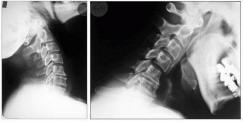

Aufnahmen von der Wirbelsäule zur Beurteilung von Veränderungen am Knochen, vor Operationen, zum Ausschluß von Knochenbrüchen und zur Verlaufskontrolle. Eine spezielle Vorbereitung der Patienten ist nicht notwendig. Moderne Röntgengeräte fertigen solche Aufnahmen mit einer geringen Strahlendosis an. Für alle, die sich genauer über die Auswirkung von Strahlen informieren wollen, empfiehlt sich ein Blick in Wikipedia.

Dies sind Röntgenaufnahmen von derselben Stelle, die in verschiedenen Körperpositionen aufgenommen werden, bei der Wirbelsäule zumeist in Vor- und Rückneigung. Sie dienen der Diagnose von Gleitwirbeln.